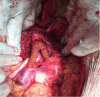

Infectious aneurysms, formerly known as mycotic aneurysms, are rare, most often involve the aorta in young patients, and have a greater tendency to rupture than aneurysms of other etiologies. The most characteristic shape is saccular and the most common etiologic agents are Staphylococcus sp. and Salmonella sp. There is scant and imprecise information in the literature about correct nomenclature, diagnosis, and treatment. The authors present three cases in which diagnostic and therapeutic procedures were documented. In addition to reporting this case series, the authors also present a review of the subject, outlining pertinent diagnostic and therapeutic strategies.